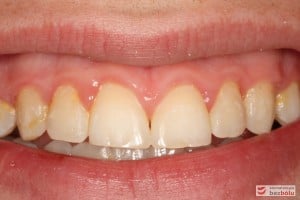

Rodzice zgłosili się z pacjentem celem rutynowej kontroli ortodontycznej. Wykonano OPG i po analizie modeli diagnostycznych stwierdzono brak miejsca dla wyrzynania dolnej prawej piątki stałej oraz zwężenie szczęki wraz z rotacją górnych zębów szóstych. W łuku górnym w pierwszym etapie leczenia zastosowano Rotator, celem odrotowania 6-tek stałych oraz ekspansji łuku w wymiarze poprzecznym. Następnie zamontowano aparat stały metalowy do uszeregowania zębów w łuku. W łuku dolnym miejsce odtwarzano stosując aparat stały i odpowiednią mechanikę leczenia. Leczenie aktywne trwało 3,5 roku, po czym zastosowano terapię retencyjną (retainer stały w żuchwie oraz Płytkę Hawley’a w szczęce).